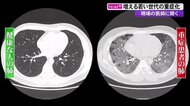

基礎疾患がなくても…若い世代の重症化が増加 コロナ治療にあたる医師「“うつぶせ”の姿勢で肺を守る」【高知発】